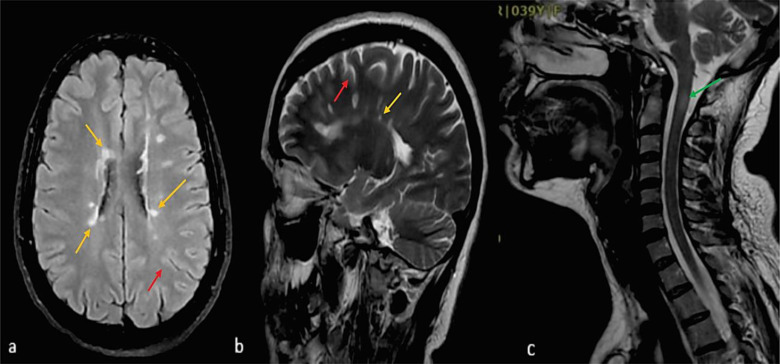

背景:多发性硬化症(MS)是导致年轻人非创伤性残疾的最常见原因。关于接种 2019 年冠状病毒病(COVID-19)疫苗后发生脱髓鞘事件的报道很有限。接种方法我们报告了所有在2021年9月至2022年6月期间新诊断为多发性硬化症且近期(≤6周)接触过国药集团(BBIBP-CorV)疫苗的患者(n = 8)。我们还查阅了截至 2023 年 9 月发表的相关文献。结果在研究期间,338 名新确诊的多发性硬化症患者到我们的多发性硬化症三级转诊中心就诊,其中 8 人(2.36%)在接种国药控股疫苗后首次脱髓鞘发作,中位间隔为 2 [2.0, 4.0] 周(性别比为 1:1,中位年龄:20.5 [18.0, 27.0] 岁)。除一名患者有潜在脱髓鞘病史和另一名患者有免疫性血小板减少性紫癜(ITP)家族史外,其他患者均无自身免疫/神经系统疾病的个人或家族病史。所有患者均有脱髓鞘性脑部磁共振成像病变,其中4人的颈脊髓受累。最常受影响的脑区是脑室周围和皮层下区域。所有患者的寡克隆带(OCB)均呈阳性,支持多发性硬化症的诊断。所有患者均被诊断为复发性多发性硬化症,并接受了单独或结合血浆置换的静脉甲基强的松龙(IVMP)治疗(3/8)。利妥昔单抗是最常用的疾病修饰治疗方法(3/8)。结论本研究提供了初步证据,证明国药控股疫苗与多发性硬化症初期表现之间存在潜在联系。然而,要证实这种关联并确定其潜在机制,还需要进行更大规模的对照组研究和长期随访。

Background: Multiple sclerosis (MS) is the most common cause of non-traumatic disability in young individuals. There are limited reports of developing demyelinating events following the coronavirus disease 2019 (COVID-19) vaccination. Methods: We reported all individuals (n = 8) with new MS diagnoses with recent exposure (≤ 6 weeks) to the Sinopharm (BBIBP-CorV) vaccine between September 2021 and June 2022. We also reviewed the related literature published as of September 2023. Results: Of 338 newly diagnosed patients with MS who attended our tertiary referral MS center during the study period, 8 (2.36%) had their first demyelinating attack with a median interval of 2 [2.0, 4.0] weeks following the Sinopharm vaccine (sex ratio 1:1, median age: 20.5 [18.0, 27.0] years). No personal or family history of autoimmune/neurological disorders was documented, except for one patient's history of a previous potential demyelinating event and another's family history of immune thrombocytopenic purpura (ITP). All patients had demyelinating brain MRI lesions, and 4 had cervical spinal cord involvement. The brain areas most commonly affected were the periventricular and subcortical regions. Positive oligoclonal bands (OCBs) in all patients supported the MS diagnosis. All patients were diagnosed with relapsing-remitting MS and received intravenous methylprednisolone (IVMP) alone or in combination with plasma exchange (3/8). Rituximab was the most frequently used disease-modifying treatment (3/8). Conclusion: This study provides preliminary evidence of a potential association between the Sinopharm vaccine and the initial manifestations of MS. However, further larger-scale studies with control groups and long-term follow-ups are needed to confirm this association and determine the underlying mechanisms.